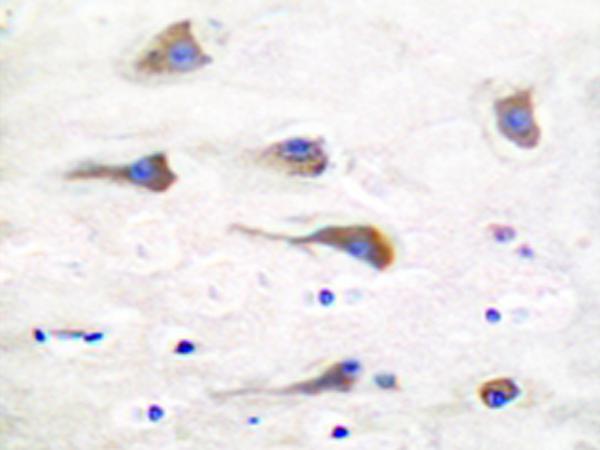

IHC positive control:

|

Human brain tissue

IHC Recommend dilution:

50-100